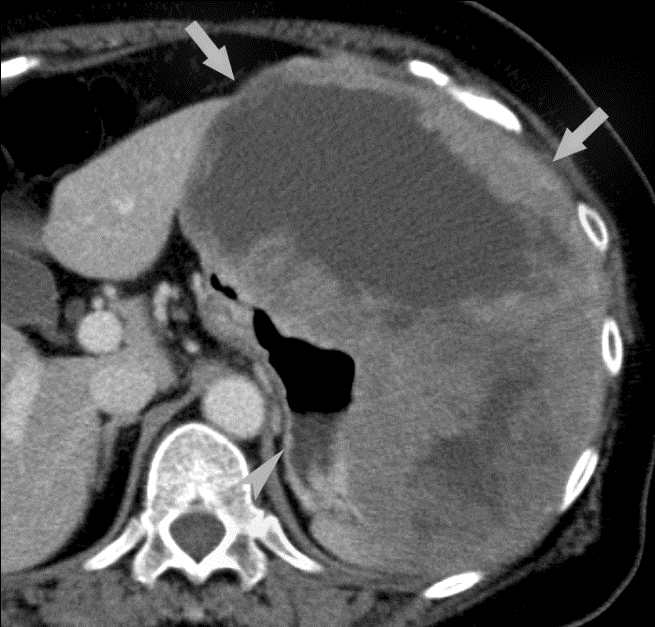

Stomach cancer CT wikidoc Gastric Cancer Chest X Ray International guidelines on clinical staging of gastric cancer recommend the use of. It might also be used to help determine if a person has any serious lung. Gastric cancer, also known as stomach cancer or gastric carcinoma, refers to a cancer that arises from the mucosal lining of. Surgical resection is the only cure. This test can help show if. Gastric Cancer Chest X Ray.

Gastric Cancer at the EG Junction Stomach Case Studies CTisus CT Gastric Cancer Chest X Ray International guidelines on clinical staging of gastric cancer recommend the use of. This test can help show if the cancer has spread to the lungs. It might also be used to help determine if a person has any serious lung. Surgical resection is the only cure. Gastric cancer, also known as stomach cancer or gastric carcinoma, refers to a cancer. Gastric Cancer Chest X Ray.